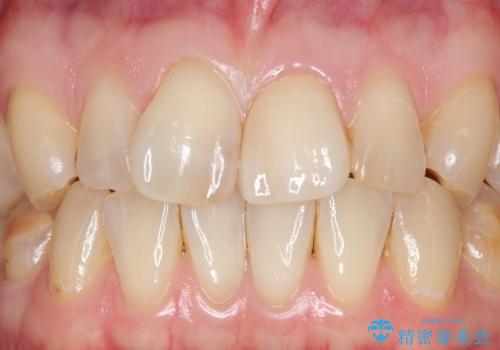

天然歯と見紛うほどの自然な仕上がりに喜んで頂けました。

クラウンの繊細なグラデーションや自然な表面性状・形態は熟練した技工士さんの技術の賜物です。

被せ物の種類:ジルコニアオールセラミッククラウン スペシャル